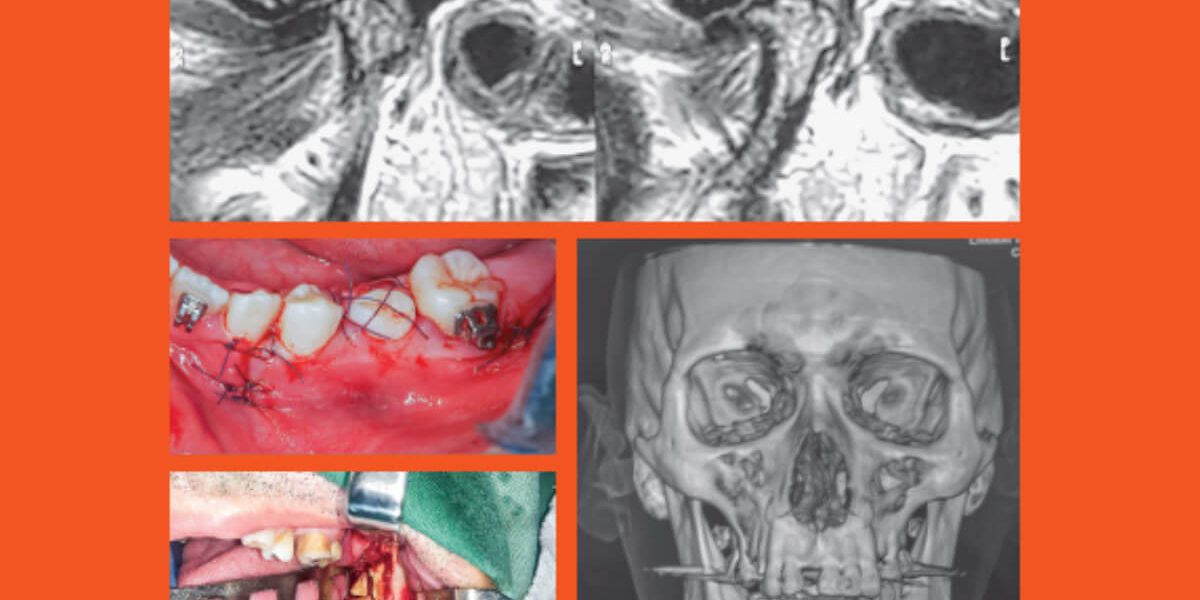

Journal of the Brazilian: College of Oral and Maxillofacial Surgery

Volume 06 | Number 3 | Sep / Dec 2020